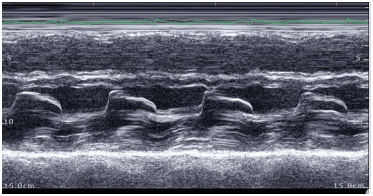

Das seguintes alternativas, assinale a que é mais compatível com disfunção sistólica do VD.

Assinale a classificação de Carpentier para a imagem abaixo.